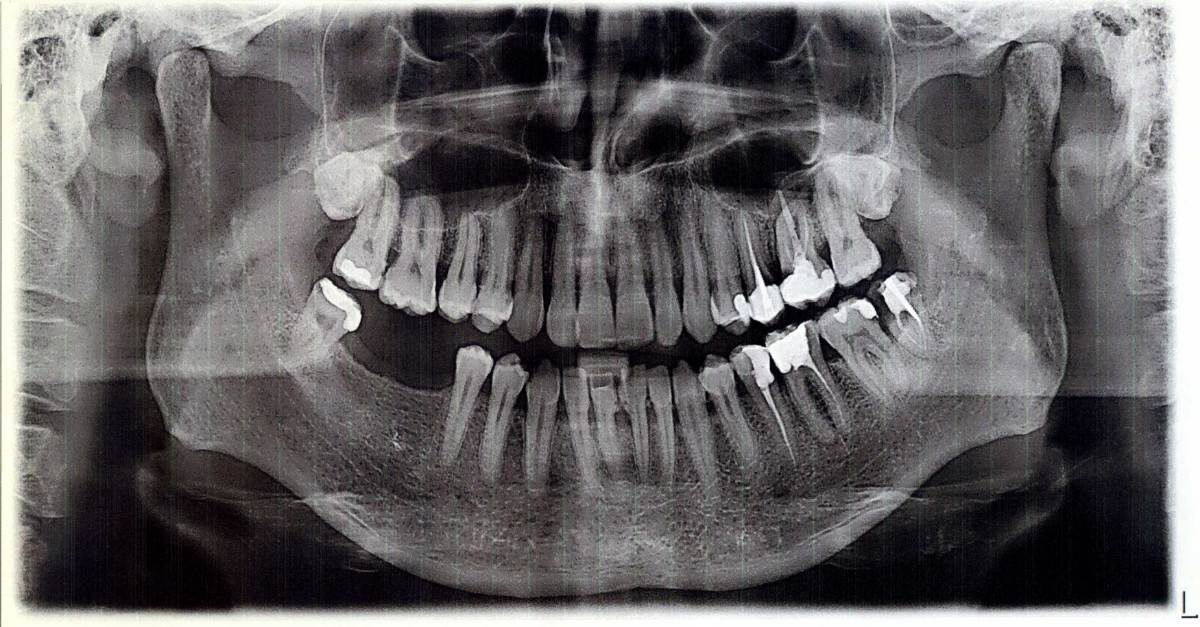

Sergey-010101 Опубликовано 11 октября, 2025 Поделиться Опубликовано 11 октября, 2025 (изменено) Здравствуйте. Можно ли мне пересадить восьмерки сверху на места шестерки и семерки снизу? Сверху по бокам это ведь восьмерки? 2018 г. 2023 г. Изменено 11 октября, 2025 пользователем Sergey-010101 Ссылка на комментарий

Женька Опубликовано 12 октября, 2025 Поделиться Опубликовано 12 октября, 2025 (изменено) @Sergey-010101 потому что зубов у Вас уже давно нет. И в Вашем случае трансплантация зубов намного сложнее технически, чем имплантация. Добавьте к этому возможную потерю ширины костной ткани (которую мы не можем оценить по данным снимкам). А те кто умеют даже в таких условиях трансплантировать зубы, как правило находятся в гораздо более высокой ценовой категории, чем в среднем по рынку. Я бы рассматривал обычную имплантацию в Вашем случае и не старался придумать велосипед. Даже если очень хочется. Даже если говорят, что дешевле. Даже, если говорят, что лучше чем имплантация. Изменено 12 октября, 2025 пользователем Женька 1 1 Ссылка на комментарий